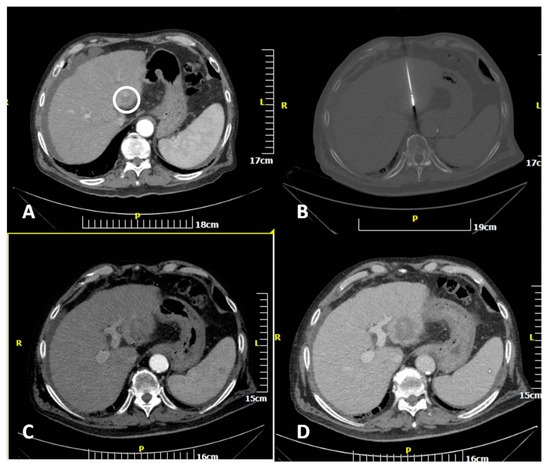

2.2. Percutaneous MW Ablation Procedure

Ablation Zone Parameters